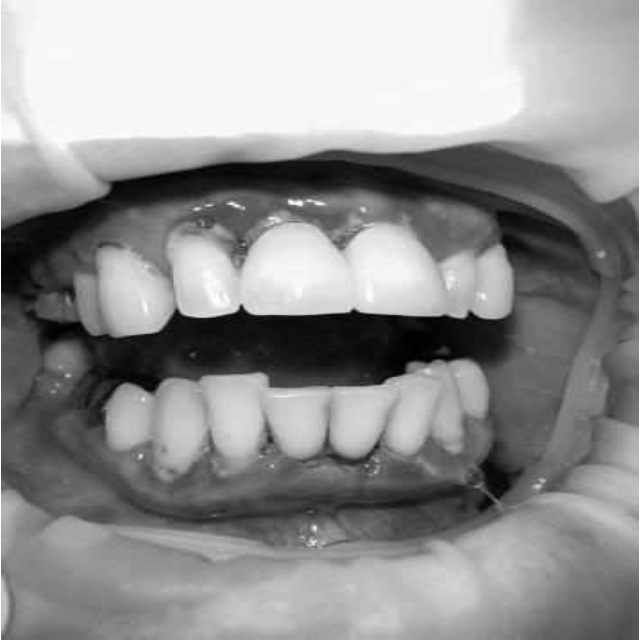

Через 6 месяцев при осмотре выявлен удовлетворительный уровень индивидуальной гигиены, отсутствие участков кровоточивости и гноетечения (рис. 4), пародонтальные карманы уменьшились в размерах (рис. 5). Пациент отмечает значительные улучшения. После стабилизации пародонтологического статуса пациент направлен для дальнейшего ортопедического лечения.

Рис. 4. Динамика результата через 6 месяцев

Рис. 5. Пародонтограмма с использованием компьютерного зондирования через 6 месяцев